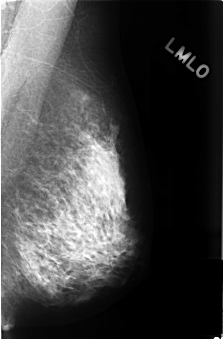

C_0413_1.LEFT_MLO

LEFT_MLO LINES 4400 PIXELS_PER_LINE 2896 BITS_PER_PIXEL 12 RESOLUTION 50 NON_OVERLAY